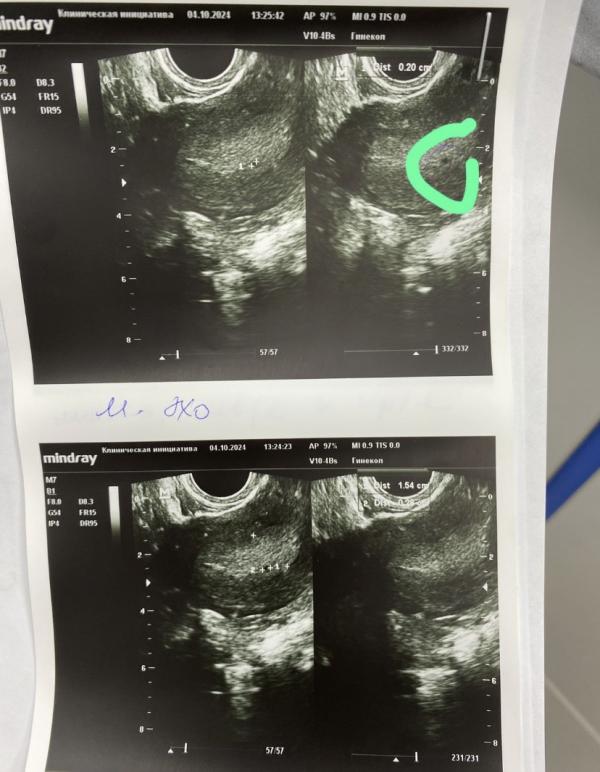

@almri, я была на УЗИ в 4,6 недель по месячным. Пя было 5 мм

Подождите немного, тяжело конечно 😁 вот ходила на узи в 6.6, пока эмбриона не было, тоже теперь жду неделю